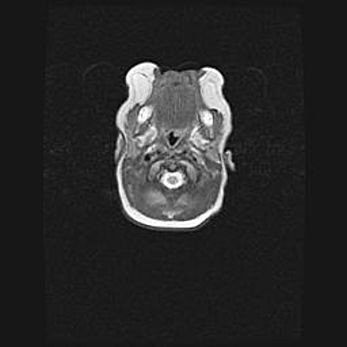

Лейкомаляция с кистозно-глиозной дегенерацией головного мозга.

Возраст: 2 месяца 25 дней

Вес: 6400 г

Окружность головы: 40 см

Срок гестации: 41 неделя

Лейкомаляцию относят к ишемически-гипоксическим повреждениям головного мозга, диагностируемым у новорожденных. При лейкомаляции в головном мозге обнаруживают очаги некроза, возникшие после тяжелой гипоксии и нарушения кровотока. В процессе морфогенеза очаги проходят три стадии: 1) развития некроза, 2) резорбции и 3) формирования глиозного рубца или кисты. Перивентрикулярная лейкомаляция (ПЛ) встречается примерно в 12% случаев среди новорожденных, обычно – у недоношенных детей, причем, частота ее зависит от массы, с которой младенец появился на свет. Наибольшее число малышей страдает лейкомаляцией, если масса при рождении 1500-2500 г.